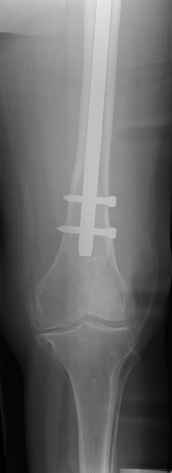

4. We could treat this fracture like there is no a nail - new locking plates allow for secure fixation.... two similar cases are attached...

Images sent by Professor Kanlic look nice, very good job. Excellent achorage in distal fragment. However, unicortical screwing or bicortical

makes a difference, also for locked screws. Proximal fragment unicortical fixation may present stability not easlily predictable. Certainly its stability for wheelchair should be sufficient. Full weight bearing can not be mentioned for this case. If minimal bearing is allowed full weight

single step may happen in elderly.

Gamma nail exchange may probably fit the criteria of optimal and minimal invasivness, indeed. Removal could be relatively fast due to large intramedullary diameter seen on X-ray.

I do agree that distal locking of the nail in distal femur remains critical.

Our experience with locking plates in osteoporoticbone and weight bearing is that there's no difference with a nail. the old patient start walking with crutches and 20kg weight bearing as the general conditions are good as for the nail. In this case 13 holes LISS with at least 8 cortex proximally

Dear Sir, in my opinion it's better to take off the gamma nail, anatomically reduce the spiral with 2 lag screws, and fix the shaft fracture with a LISS-LCP 13 holes. No bone graft. Immediate mobilization and weight bearing.